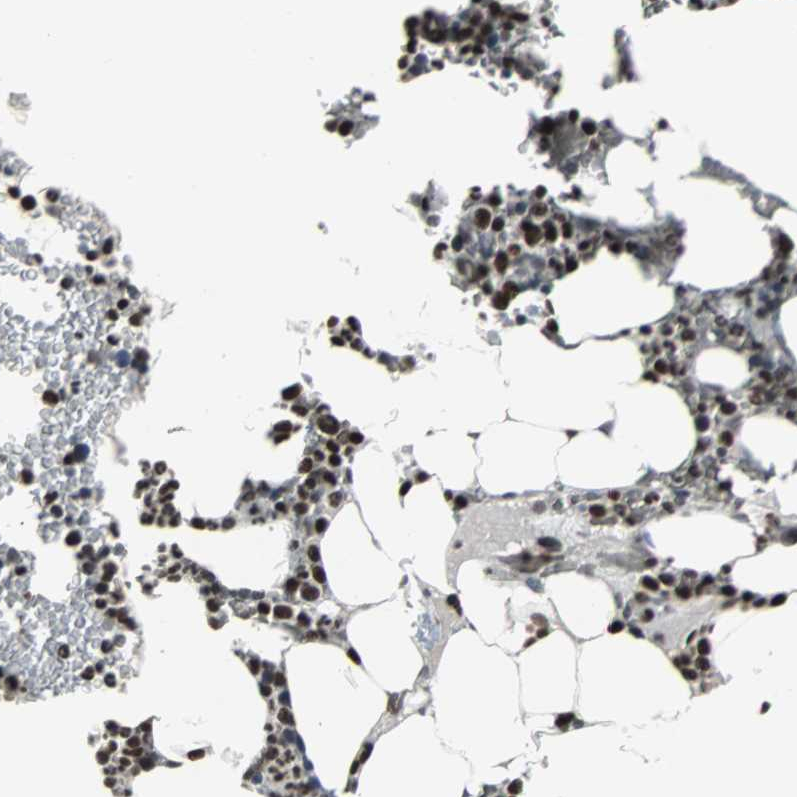

Immunohistochemical staining of human bone marrow shows strong nuclear positivity in hematopoietic cells.